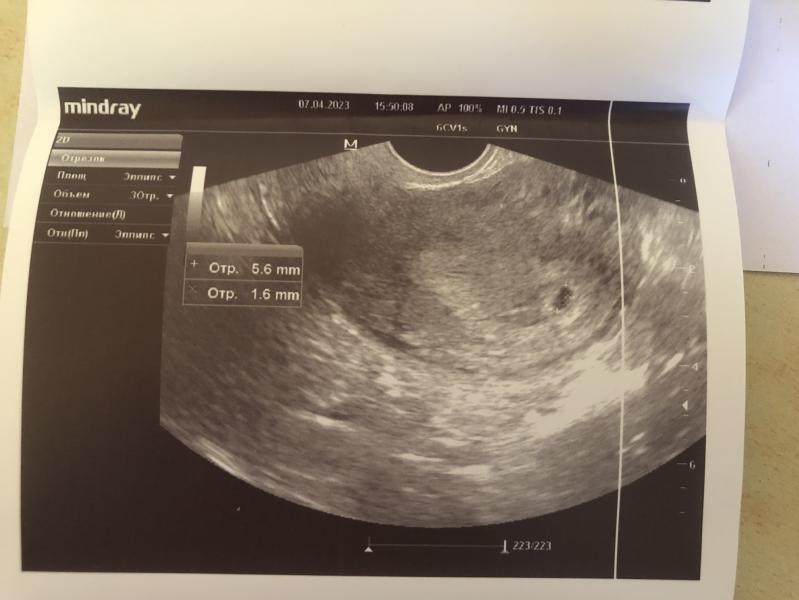

Лёгкой беременности и здорового малыша! Я до сих пор, глядя на такие снимки, в шоке от того, как из такой маленькой горошины вырастает целый человек😍